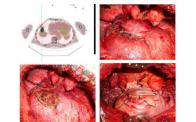

Chest wall resection and reconstruction